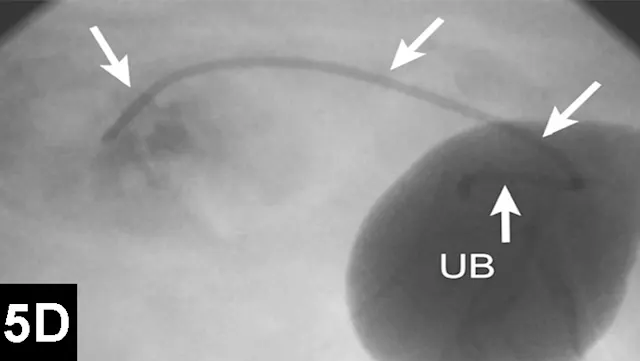

Similar techniques are currently being employed to manage ureteral obstructions secondary to uroliths, strictures, or malignancies (Figure 5). These procedures can be performed surgically or with minimal invasiveness (percutaneously or via cystoscopy) to reduce morbidity and improve outcomes in cats and dogs.9 For example, dogs with ureteral obstructions can now be treated through a small needle stick through the flank or endoscopically to relieve the obstruction and be discharged on an outpatient basis.

Figure 5A: Serial lateral fluoroscopic images of a dog with ureteral obstruction secondary to trigonal transitional cell carcinoma.

Ultrasound-guided 18-gauge needle access into the renal pelvis with subsequent contrast ureteropyelogram demonstrating hydronephrosis and hydroureter (white arrows). A colonic marker catheter (black arrows) aids in radiographic magnification and stent length determination.